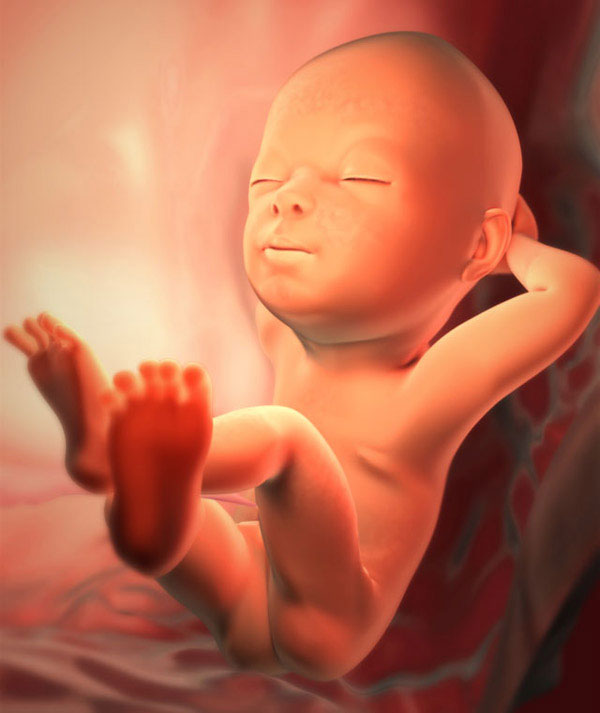

29e semaine de grossesse. Le poids du fœtus est d'environ 1,4 kg, la longueur totale du corps est d'environ 38 cm Il est temps pour la future mère de maîtriser la méthode de calcul des mouvements.

Qu'arrive-t-il au bébé

Maintenant, le bébé grandit et consolide ses réalisations antérieures. Le développement le plus actif de la graisse sous-cutanée se poursuit, et pas seulement celui habituel de toute personne. Le fœtus forme également une graisse brune spéciale. Lorsque le bébé est né, cette substance le protégera parfaitement du froid. Ceci est important, car la régulation de la chaleur chez les nouveau-nés n'est pas immédiatement établie.

De plus, la formation d'émail dentaire sur les rudiments des dents primaires se poursuit. Le squelette du fœtus est encore activement minéralisé. Cela nécessite environ 250 mg de calcium par jour. Il y a donc des produits laitiers dont vous avez besoin tous les jours. Si le calcium ne suffit pas, il commence à être littéralement lavé des os de maman. Les dents sont touchées en premier, elles deviennent cassantes, sensibles. Si vous remarquez ce symptôme, parlez-en d'urgence à votre médecin. Vous pourriez avoir besoin de suppléments de calcium dans votre situation.

Que sait-on d'autre sur le développement fœtal:

- améliorer le foie, les poumons;

- le pancréas et le cortex surrénalien produisent déjà des hormones;

- la quantité de lubrifiant cutané et de poils vellus dans tout le corps est réduite.

Comment se trouve le fœtus maintenant? Beaucoup d'enfants se sont déjà installés correctement, c'est-à-dire tête baissée. Mais la position du corps du bébé peut ne pas encore changer une fois avant la naissance. Maintenant, il n'y a aucune raison de s'inquiéter. Lorsque deux enfants grandissent immédiatement sous le cœur de la mère, ils sont plus à l'étroit, moins de place pour les coups d'État. Mais les jumeaux à cette période n'occupent pas toujours la bonne position.